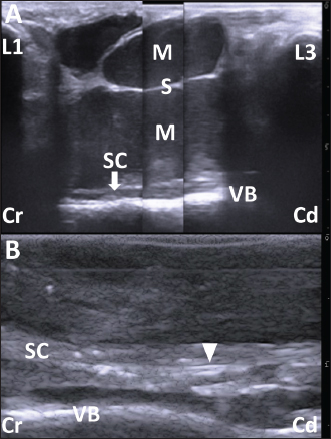

A portable-type ultrasound device (MyLabOne VET, Esaote Corporation, Genova, Italy) was used to observe the internal structures of its back’s swelling while scanning subcutaneously at a cranial-caudal longitudinal axis of its back using a 5.0-MHz linear transducer. On the ultrasonograms showing the areas cranially and caudally to the swollen mass structures, the spinous process of the first and third lumbar vertebras (L1 and L3) were seen as hyperechoic, curved lines accompanied by posterior acoustic shadowing (Fig. 2A). However, no echotexture was evident in the spinous process of the second lumbar vertebra (L2). The mass structure fully occupied the space between the spinous process of the L1 and L3. The superficial areas of the mass were ultrasonographically characterized by formations of two large, well-defined compartments of the cystic lesions. At the cranial part of the mass, two superficial cystic lesions were seen as a flat triangle structure, measuring roughly 1.5 and 2 cm in dorsal-ventral height and cranial-caudal length, respectively. The elliptical caudal part had approximately 2 and 3 cm in height and length, respectively. Within the lumens of these two cystic lesions, the contents were commonly anechoic without hyperechoic deposits. One deeper, larger cystic lesion was formed by hyperechoic membranous structures, allowing clear separation from the two superficial cystic lesions. The triple, parallel, echogenic lines running along this lesion defined the deepest part of this lesion. However, the cranial and caudal edges of the deeper cystic lesion were unclear. The height of the deeper cystic lesion could be measured at approximately 3.5 cm. Within the triple-lined structure, visualized as homogenously hypoechoic, the echogenicity was higher in the dorsal and ventral lines than in the middle line. Based on the ultrasonographic characteristics of the triple-lined structure, the dorsal and ventral hyperechoic lines were the dura membranes, and the thinner middle line was the central canal. Within the echotexture of the spinal cord, the hyperechoic line of the central canal was interrupted. The diameter of the central canal mostly kept the same thickness between the L1 and L3, and measured 5–7 mm. The echotexture of the spinal cord was laid peripheral to the thickened, hyperechoic line running across in the cranio-caudal direction. The ventral and osseous surfaces of the vertebral canal were identified between the L1 and L3.

Fig. 2. (A) The ultrasonogram of the mass when scanning longitudinally along the swollen back using a 5.0 MHz linear transducer. This image is created by merging three sections of two ultrasonograms. The hypoechoic capsular mass (M) separated into three parts by the echogenic septal structures (S) is evident within the space between the hyperechoic structures of the spinous process of the first and third lumbar vertebras (L1 and L3, respectively). The cystic mass extends by 7 cm in depth and is close to the thin, hypoechoic structure of the spinal cord (SC), outlined by the hyperechoic line of the dura mater. The structure of SC runs along the hyperechoic line of the spinal canal’s surface between the L1 and L3 (VB). Scale: 1 cm. (B) The intraoperative ultrasonogram of SC is represented as a heterogeneous echogenic structure outlined by the hyperechoic lines. The SC runs along the VB within the hypoechoic background of the saline pool. The double hyperechoic lines (arrowhead) outline the distended central canal. Cr: Cranial; Cd: Caudal. Scale: 5 mm.

One day after the clinical examination, the animal was anesthetized using the same method as in the imaging examinations. The swollen skin was shaved, disinfected, and injected subcutaneously with lidocaine hydrochloride (xylocaine injection 2%; AstraZeneca K. K., Osaka, Japan). A 20 cm long crescent-shaped skin incision was made along the left margin of the mass (Fig. 3A). Blunt dissection of the subcutaneous tissues led to the exposure of the dark-red surface of the mass, located between the spinous process of the L1 and L3, which could be palpated by the operator’s finger (Fig. 3B). The mass could be separated from the adjacent soft tissue layers by dissecting the right-sided border bluntly and using an electric scalpel, while care was taken to prevent the mass’s rupture (Fig. 3C). Subsequently, the mass could be separated circumferentially when the dissection was extended from right to left (Fig. 3D). When the operator’s finger was inserted deeper than the mass along the left-sided, separated space, adhesion between the dura mater and the ventral mass’s surface could be felt. When the mass was carefully lifted, the spinal cord could be seen to rise upward while sticking to the ventral mass’s surface (Fig. 3E). The adhesion could be released by carefully separating the fibrous connective tissues that had formed between the dura mater and the ventral mass’s surface while the mass was brought upward. A disposable ultrasound probe cover (Echo Probe Cover II, Fuji Medical Company, Ltd., Tokyo, Japan) was used to observe the spinal cord intraoperatively once it was released from the now-removed mass’s compression. The covering of a 10 MHz linear transducer was prepared by pouring an ultrasound gel inside the cover, allowing good attachment between the cover’s inner surface and the transducer’s surface. The covered transducer was inserted into the space of the removed mass, which had been filled with hot sterile saline water (Fig. 3F). Ultrasonographically, the spinal cord presented as a heterogeneous echogenic structure outlined by hyperechoic lines running within the hypoechoic background of the saline pool (Fig. 2B). The hyperechoic line of the central canal was interrupted and partly distended. Double hyperechoic lines outlined the distended central canal. The width of the spinal cord measured 3.4–4.2 mm on the same ultrasonogram. After continuous lavage into the space of the removed mass with saline fluid, the muscular fascia was separated from the surfaces of the both-sided longissimus dorsi muscles at the level of the L1 and L3 (Fig. 3G). The separation of the muscular fascia extended as deeply as possible so it could be used as a muscular flap to shorten the dead space left by the now-removed subcutaneous mass. Both sides of the separated muscular fascia were reversed toward the space of the removed mass and sutured using an absorbable suture material (MAXON; Davis and Geck Inc., Brooklyn, NY) (Fig. 3H). The incised skin was closed using a nylon suture material (Suprylon USP0, Vömel, Gronberg, Germany) (Fig. 3I).

In the present case, ultrasonography and myelography, followed by CT myelography, were successfully utilized to obtain the diagnostic evidence. This evidence found that the subcutaneous abscess could contribute to spinal cord compression via a congenital defect of the spinous process. An ultrasound transducer with a lower frequency should be used to detect the subcutaneous mass’s invasion into deeper structures, including the spinal cord, because the higher frequency of ultrasound can contribute to higher resolution images of superficial mass lesions, but cause poor visibility of the deeper structures (Squire et al., 2005). The ultrasound frequency in the transducer used for the previous calves with congenital spinal deformities was between 6 and 10 MHz (Testoni et al., 2010, 2012). An ultrasound frequency of 5 to 7.5 MHz was required for the atlanto-occipital space of adult cattle (Braun and Attiger, 2016). Ultrasonographic visibility of the spinal cord within the cranial lumbar or thoracic vertebras is commonly poor. This is due to the extended distance between the skin and vertebral canal, dependent on the longer spinous process, compared with the caudal parts of the lumbar vertebras and cranial parts of the cervical vertebras, for which ultrasonography can allow demonstration of the spinal cords (Testoni et al., 2010, 2012; Braun and Attiger, 2016). Thus, a lower ultrasound frequency (<6 MHz) may be required for these regions, despite this ultrasound level not always allowing visualization of the spinal cord (Testoni et al., 2010, 2012). Longitudinal ultrasonography of the spinal cord on the levels of cervical and lumbar vertebras can provide the normal appearance of the hypoechoic spinal cord lined by the hyperechoic dura mater, along the center of which the hyperechoic line of the central canal (Testoni et al., 2012; Braun and Attiger, 2016). The spinal cord’s echotextures are interrupted by the extremely hyperechoic structures of the dorsal surfaces of the vertebras (Testoni et al., 2012). On the ultrasonogram in the present case, when scanning the swollen back longitudinally, the spinal cord could be observed over the entire layer at approximately 7 cm depth, at the level of L2 and L3. The defects in the vertebral laminae and the spinous process can be a good window, allowing penetration of ultrasound waves generated from the ultrasound transducer applied to the back (Hudson et al., 1998). However, the pathological defect of the vertebral laminae was too small to demonstrate the spinal cord compression associated with the subcutaneous mass when scanning on the swollen surface of the skin (Braun et al., 2016). Even if presenting no congenital defects in the vertebral laminae and spinous process, percutaneous ultrasonographic scanning may provide diagnostic evidence of spinal cord compression in animals with progressive back abscessations, inducing bone destruction of the underlying vertebras (Correa et al., 2013; Panziera et al., 2016). In the present case, longitudinal spinal ultrasonography could not identify the common ultrasonographic signs of spinal cord compression, such as an extended anechoic central canal surrounded by a hyperechoic dura-arachnoid layer, and the decreased thickness of the spinal cord (Testoni et al., 2010, 2012). Myelography was previously utilized to confirm the association between the spinal cord and subcutaneous back masses such as spina bifida cystica and lipoma (Kieck and De Villiers, 1975; Boyd, 1985; Zani et al., 2008; Toma et al., 2021). On the myelogram, the flow’s interception of the intradural contrast medium is a common sign at the location of spinal cord compression (Koç et al., 1998). In the present case, CT myelography allowed the identification of the mechanical compression of the spinal cord due to the weight of the adjacent mass based on the interception of the enhanced lines representing the intradural flows at the affected level. This finding suggests the etiology of the animal’s progressive paralysis of its hindlimb, associated with the back mass’s growth (Koç et al., 1998). Additionally, the 3D-CT could be utilized for evaluating the etiology and surgical planning, because clarifying the location of the defected spinous process corresponds to the area of the intercepted, enhanced line of the spinal cord on the sagittal reconstructed CT myelography.

Intraoperative uses of spinal ultrasonography have been developed in human medicine using a 3.5–7.5 MHz transducer covered with a sterile globe and sheath (Dohrmann and Rubin, 1982; Knake et al., 1983; Quencer and Montalvo, 1984; Quencer et al., 1984; Feldenzer et al., 1986; Falcone et al., 1994; Ganau et al., 2018). A saline pool procedure—scanning the spinal cord within a surgical site filled with a sterile saline solution—has been used in most of the previous human and veterinary reports, and our scanning method is identical (Knake et al., 1983; Quencer and Montalvo, 1984; Quencer et al., 1984; Feldenzer et al., 1986; Nakayama, 1993; Falcone et al., 1994; Finn-Bodner et al., 1995; Mak et al., 1996; Galloway et al., 1999; Tanaka et al., 2006; Nanai et al., 2006, 2007; Bonelli et al., 2015; Ganau et al., 2018). The saline bath is useful to avoid direct contact of the applied transducer with the spinal cord (Ganau et al., 2018). The normal longitudinal echotexture of the spinal cord is a homogenous hypoechoic structure outlined as hyperechoic within the anechoic fluid contents, including hyperechoic floating bubbles (Quencer and Montalvo, 1984). The central canals are normally represented by hyperechoic lines of various widths running along the center of the spinal cord or are invisible (Quencer and Montalvo, 1984). When compared to normal spinal echotexture, the pathological structures of the spinal cords can be well identified on intraoperative spinal ultrasonograms; a variety of size, shape, and echogenicity in the intraspinal mass lesions can allow differentiation of the cysts, tumors, and small intramedullary foci associated with spinal centesis (Dohrmann and Rubin, 1982; Knake et al., 1983; Quencer et al., 1984). Previous human reports examined the therapeutic efficacy of spinal ultrasonography used during laparotomy, followed by surgical resection of epidural abscess; this technique could provide effective information on the masses, such as their locations and anteroposterior extensions, and degrees of compression that narrow and deform the spinal cords (Feldenzer et al., 1986; Mak et al., 1996; Ganau et al., 2018). The extended central canal can be created by compression from intraspinal or epidural masses (Dohrmann and Rubin, 1982). These ultrasonographic findings are helpful for the intraoperative planning and subsequent removal of the masses (Feldenzer et al., 1986; Mak et al., 1996). Additionally, the real-time images obtained from this technique are useful for assisting needle biopsy, drainage, and shunt placement (Knake et al., 1983; Quencer et al., 1984; Feldenzer et al., 1986; Mak et al., 1996; Morita et al., 2019b). Intraoperative scanning is very useful for evaluating surgical achievement of spinal decompression and retropulsion after removing epidural masses (Quencer et al., 1984; Feldenzer et al., 1986; Ganau et al., 2018). In the previous canine and feline cases, ultrasonography was also used for intraoperative identification of the pathological regions of the spinal cords while scanning through an opening of the vertebral lanima created with laminectomy for surgical decompression in intravertebral disc herniation and Wobbler syndrome, and surgical resection in spinal arachnoid cysts and various spinal tumors (Nakayama, 1993; Galloway et al., 1999; Nanai et al., 2006; Bonelli et al., 2015). In small animals, the ultrasound frequency of the probe used for intraoperative spinal ultrasonography varied between 5 and 15 MHz (Nakayama, 1993; Finn-Bodner et al., 1995; Galloway et al., 1999; Tanaka et al., 2006; Nanai et al., 2006, 2007; Bonelli et al., 2015). The recommended ultrasound frequency is between 7.5 and 12.0 MHz for demonstration of small-sized structures of the spinal cord in small animals (Hudson et al., 1998). Abnormal echotexture of the affected spinal cords includes an increased echogenicity in the spinal cord affecting intraparenchymal hemorrhage, and the diffuse or focal hyperechoic changes in the trauma-induced injured spinal cord (Finn-Bodner et al., 1995; Hudson et al., 1998). Well-defined, hyperechoic lesions of the swollen spinal cords accompanying with disruption and loss of the central canal’s line can represent intraspinal mass formation (Hudson et al., 1998; Nanai et al., 2006, 2007; Bonelli et al., 2015). In the present case, the abnormal echotexture of the spinal cord could suggest a severe spinal damage, when scanning using ultrasonography through the defected vertebral laminae and spinous process after removal of the mass. In human patients, the degree of spinal damage after removing the causative lesions can predict postoperative clinical improvements (Quencer et al., 1984; Feldenzer et al., 1986; Ganau et al., 2018). Spinal cord compression can induce posttraumatic myelopathy and myelomalacia, resulting in poor postoperative course after spinal decompression (Nakayama, 1993; Falcone et al., 1994; Tanaka et al., 2006). Posttraumatic myelopathy is represented as a heterogenous pattern of spinal cord’s echogenicity together with the formation of small microcysts (Falcone et al., 1994). Echotexture of myelomalacia seems to be characterized by a mixture of the echogenic changes within the affected spinal cord including an unclear central canal’s line (Nakayama, 1993; Tanaka et al., 2006). Doppler ultrasonography helped identify intraspinal mass invasion and judge decompression due to pulsatile microcirculation (Hudson et al., 1998; Tanaka et al., 2006; Nanai et al., 2006, 2007). Lack of vascularization within the compressed spinal cord may lead to the diagnosing of myelomalacia (Bonelli et al., 2015). Thus, Doppler ultrasound scanning would be required in intraoperative spinal ultrasonography for the bovine case.